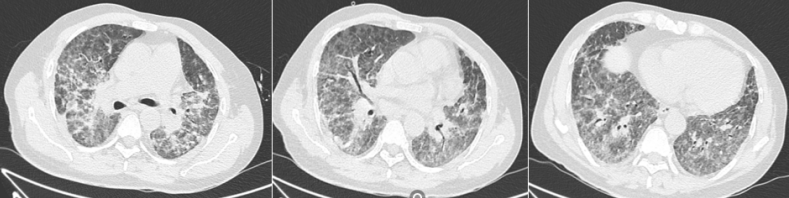

化疗1周期后,CT可见病灶明显吸收,化疗3周期后,胸部CT可见病变基本全部吸收(图2)。后续复查肺部基本恢复正常。

图片

图2  患者化疗一周期和三周期后胸部CT